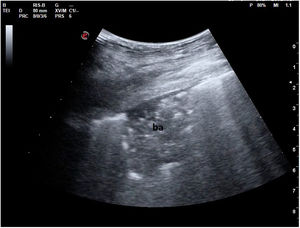

El plano paraesternal de eje largo se obtiene con la sonda sobre el segundo o el tercer espacio intercostal izquierdo, próxima al esternón y perpendicular a la piel, sobre una línea que une el hombro derecho con la cadera izquierda (fig. 2). La zona más próxima al transductor es la pared anterior del ventrículo derecho (VD), siendo también visibles la válvula mitral, la válvula aórtica (valva coronaria derecha y no coronaria), el ventrículo izquierdo (VI), la aurícula izquierda (AI), el tracto de salida del VI con la raíz aórtica, parte de la aorta ascendente y el pericardio. Si el corte es bueno, el septo interventricular anterior y la pared anterior de la aorta deben estar alineadas al mismo nivel y dispuestas de forma perpendicular al plano de estudio. La válvula mitral aparece en el centro de la imagen, de forma que su valva anterior se continúa con la pared posterior de la aorta. La aorta descendente puede verse también por detrás de la AI (fig. 3).

Las medidas a obtener en este plano son: la raíz aórtica (al principio de la sístole ventricular, con las valvas abiertas), la AI (al final de la sístole ventricular), el septo interventricular anterior y la pared posterior (en diástole) y el diámetro diastólico del VI (en telediástole y posición medioventricular, con apertura máxima).